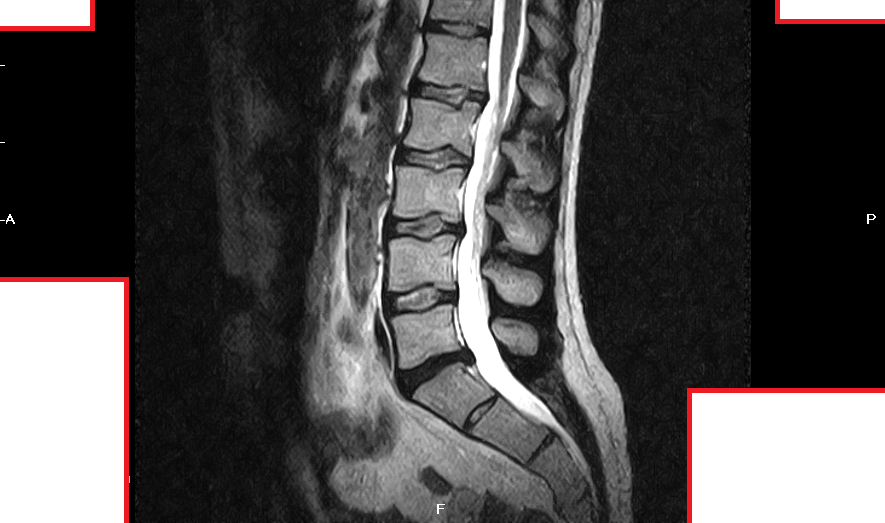

Mi sono fatto fare una risonanza magnetica senza contrasto presso un centro specialistico e la diagnosi è stata la seguente:

RM RACHIDE LOMBOSACRALE

Indagine eseguita mediante apparecchiatura a basso campo (0,4T con magnete aperto). Motivo dell'indagine: lombalgia acuta. Dall'anamnesi si rileva sciatalgia destra.

Il canale spinale ha normali dimensioni.

Modificazioni degenerative del disco L5/S1 caratterizzate da riduzione dello spessore, iposegnale nelle immagini T2 dipendenti per disidratazione e debordamento circonferenziale dell'anello fibroso.

Quest'ultimo presenta erniazione sottolegamentosa posteriore mediana con modesta impronta del versante anteriore del sacco durale.

Impegno da parte discale delle porzioni caudali dei forami neurali che sono ridotti d'ampiezza su base degenerativa artrosica intervertebrale posteriore e di altezza per la perdita di volume discale.

Le radici nervose L5 risultano dislocate e modestamente compresse nei recessi superiori. Minima retrolistesi di L5 su base degenerativa discale.

Debordamento circonferenziale dell'anello fibroso ad L4/L5 con modesta impronta del versante anteriore del sacco durale.

Analogo reperto anche ad L3/L4 ove è presente iniziale ernia postero-mediana. Impegno da parte discale anche delle porzioni caudali dei forami neurali di entrambi livelli ove le corrispondenti radici nervose L4 ed L3 sono tuttavia visualizzabili nei recessi superiori.

Erniazioni intraspongiose riguardano le limitanti somatiche affrontate tra L1 ed L3 e anche la limitante somatica inferiore di D11.

Normale aspetto delle restanti unità discosomatiche , delle radici nervose della cauda equina, del rigonfiamento lombare del midollo spinale e della muscolatura paravertebrale. Normale ampiezza dei forami neurali.

Allego nel post alcuni fotogrammi della risonza, non le metto tutte perchè sono tante.

chiedo scusa per il ritardo nella risposta. purtroppo le immagine che lei ha caricato non consentono di rispondere in maniera chiara in quanto mancano soprattutto le immagini in sezione assiale che andrebbero viste tutte contestualmente a quelle sagittali. (in confidenza sembrerebbe una protrusione discale).